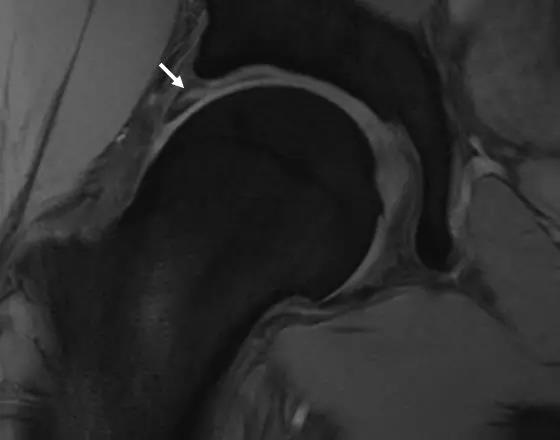

MRI表现

- 基本表现同X线。

- 对髋臼盂唇和软骨损伤的检出有较高的敏感性和特异性。

- 股骨头颈联合处前上缘骨性突起。

- 凸轮撞击型FAI--并盂唇撕裂。